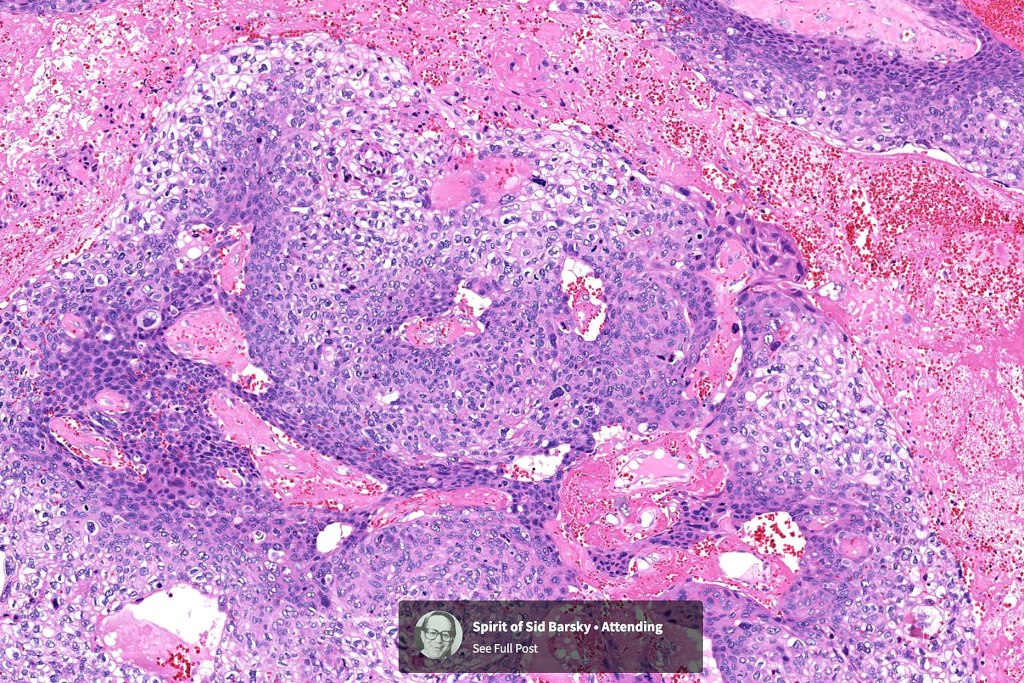

Histological features

•Infiltrating tumor arising from the wall of a pilar cyst

•Malignant change within a proliferating pilar tumor

•Nuclear pleomorphism and nuclear hyperchromatism

•Marked mitotic activity

•Abnormal mitoses

•Necrosis

•Stroma may be desmoplastic